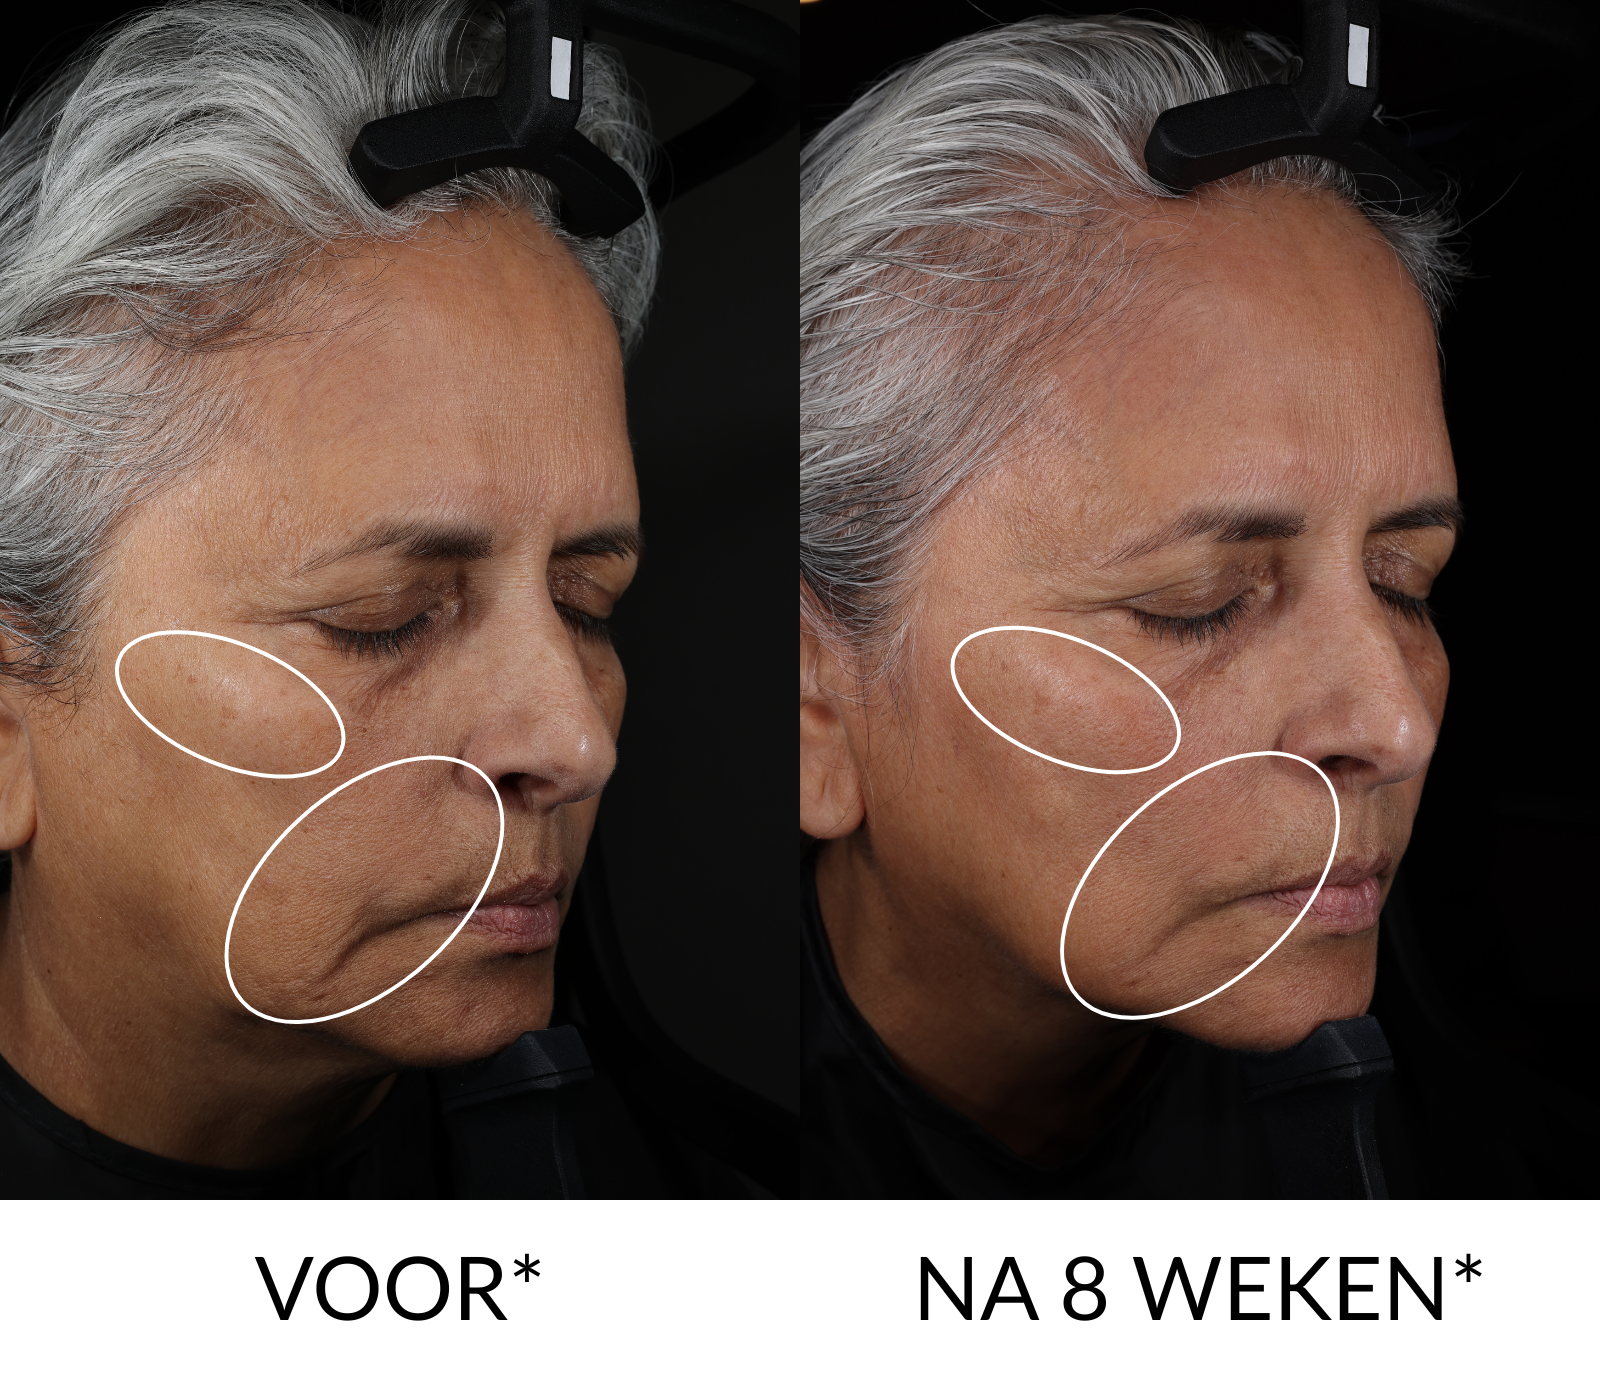

Het CellularYouth™ Longevity Serum gaat verder dan de oppervlakte en beïnvloedt het gedrag van huidcellen, zodat je huid er zichtbaar jonger uitziet dan ze werkelijk is. In slechts 8 weken zagen consumenten in klinische onderzoeken een duidelijk gladdere, stevigere en strakkere huid.

*Gebaseerd op een klinisch onderzoek van 8 weken met 32 vrouwen van 46-70 jaar, met instrumentale metingen.

- Klinisch bewezen dat het na 8 weken de zichtbaarheid van verslapping, gladheid en fijne lijntjes & rimpels verbetert***

*** Gebaseerd op een klinische studie van 8 weken met 32 vrouwen van 46-70 jaar, met dermatologische/expertbeoordeling en instrumentele metingen.